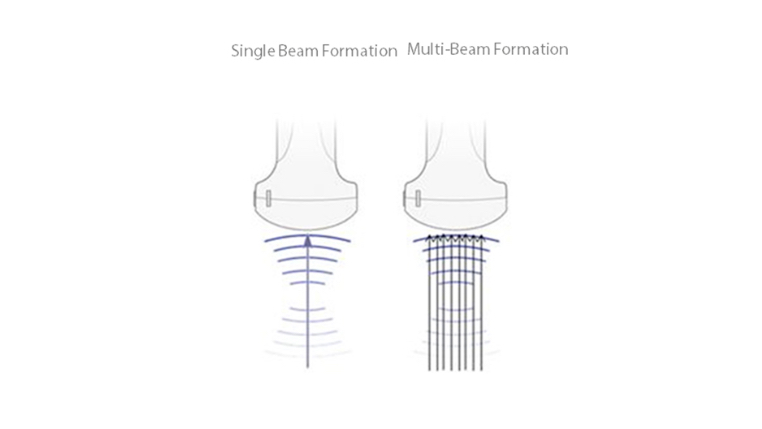

Tissue Doppler Imaging with Quantitative Analysis (TDI and TDI-QA)

Supported by MindrayŌĆÖs unique 3T technology with single crystal, the M7 premium significantly improves the performance of Tissue Doppler Imaging. With the added quantitative analysis package with comprehensive parameter outputs such as velocity, strain and strain rate, the TDI-QA performs with ease at the bedside.